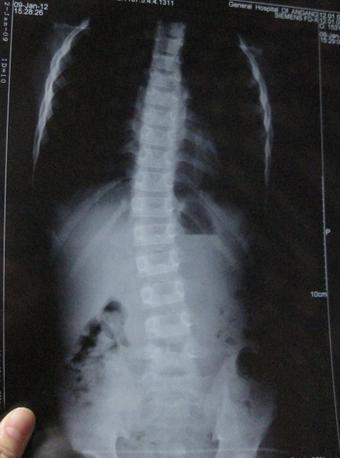

2017年7月,刚刚拿到大学录取通知书的他却出现下腰背部疼痛现象,特别是一旦遇到温度突然下降的时候,双侧髋关节疼痛为重,夜间睡觉腰背发僵,翻身困难,到当地医院检查;X线示:双侧髋关节间隙狭窄,HLA-B27(+),血沉43mm/h,诊断为:强直性脊柱炎,因为着急到校报到,未坚持系统用药治疗,病情逐渐加重,至行走困难。

(图:X线片显示季同学脊柱已经成中度弯曲)

体格检查:“4”字试验检查,臀部出现疼痛,屈腿侧存在骶髂关节疼痛;枕墙实验,枕骨结节与墙之间的水平距离开始变大,脊柱出现中度弯曲变形。

CT检查显示:脊柱出现韧带钙化、脊柱出现初期“竹节样”改变,以及椎小关节和脊柱生理曲度改变。